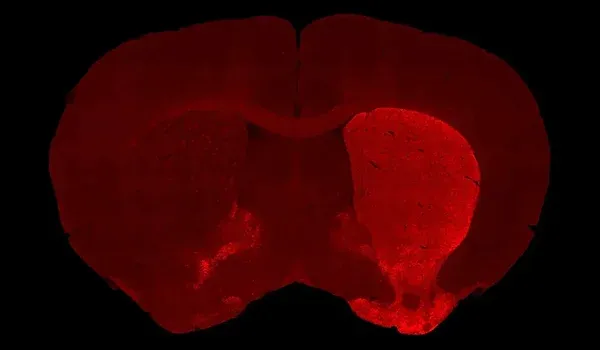

In this robust mouse model, adeno-associated virus (AAV) vectors expressing human wild-type tau (2N4R) are delivered into the substantia nigra pars compacta via stereotaxic injection. The resulting model demonstrates tau aggregates, dopaminergic neuron loss, neuroinflammation (activated microglia and astrocytes), and motor deficits reminiscent of human 4-repeat (4R) tauopathies (PSP and CBD).

In this model, adeno-associated virus (AAV) vectors encoding human wild-type 2N4R tau undergo stereotaxic injection into the midbrain substantia nigra of young adult C57BL/6 mice. This targeted intra-nigral delivery drives high levels of toxic tau expression, triggering a cascade of Parkinsonian-like pathology. Our AAV-Tau model faithfully recapitulates key hallmarks of human PSP & CBD, including:

Dopaminergic neuron loss: Substantial degeneration of dopamine-producing neurons in the substantia nigra pars compacta, with corresponding loss of dopaminergic nerve fibers in the striatum.

Tau aggregation: Accumulation of pathogenic human tau (especially phosphorylated tau), forming neurofibrillary tangle–like intracellular inclusions in affected brain regions.

Robust neuroinflammation: Pronounced activation of microglia and reactive astrocytes in areas of tau pathology, mirroring the neuroinflammatory response observed in human tauopathies.

Quantitative Histopathology (IHC/mIF): High-resolution tissue analyses to quantify PD-related pathology. We perform immunohistochemistry (IHC) and multiplex immunofluorescence for markers such as phosphorylated tau inclusions (e.g. AT8), dopaminergic neurons (tyrosine hydroxylase, TH), activated microglia (Iba1), and astrocytes (GFAP). Digital image analysis of these stained tissues provides quantitative measures of neurofibrillary tangle-like aggregates, neuronal loss, and neuroinflammation in the brain.